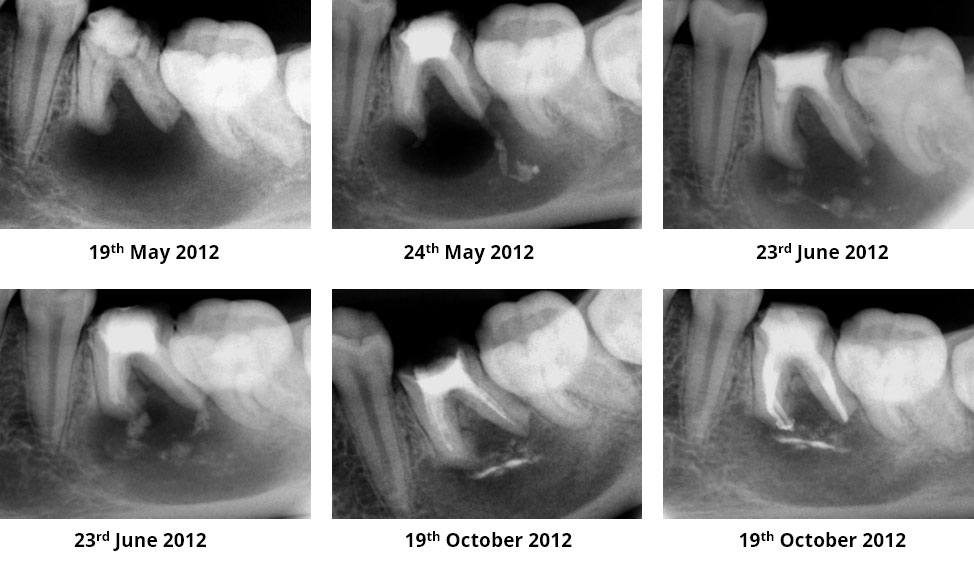

Pre-op

Pain in mandibular first molar after endo. Previous dentist unable to locate mesial canals. Obturated only the distal canal. Patient has generalized periodontal problems as well.

Pre-op, EDTA for 1 minute, After 1 minute EDTA

Red arrows show the two “white spots” indicating the calcified mesial canals.

Missed second distal canal (red arrow)

Pre-op & Post-op